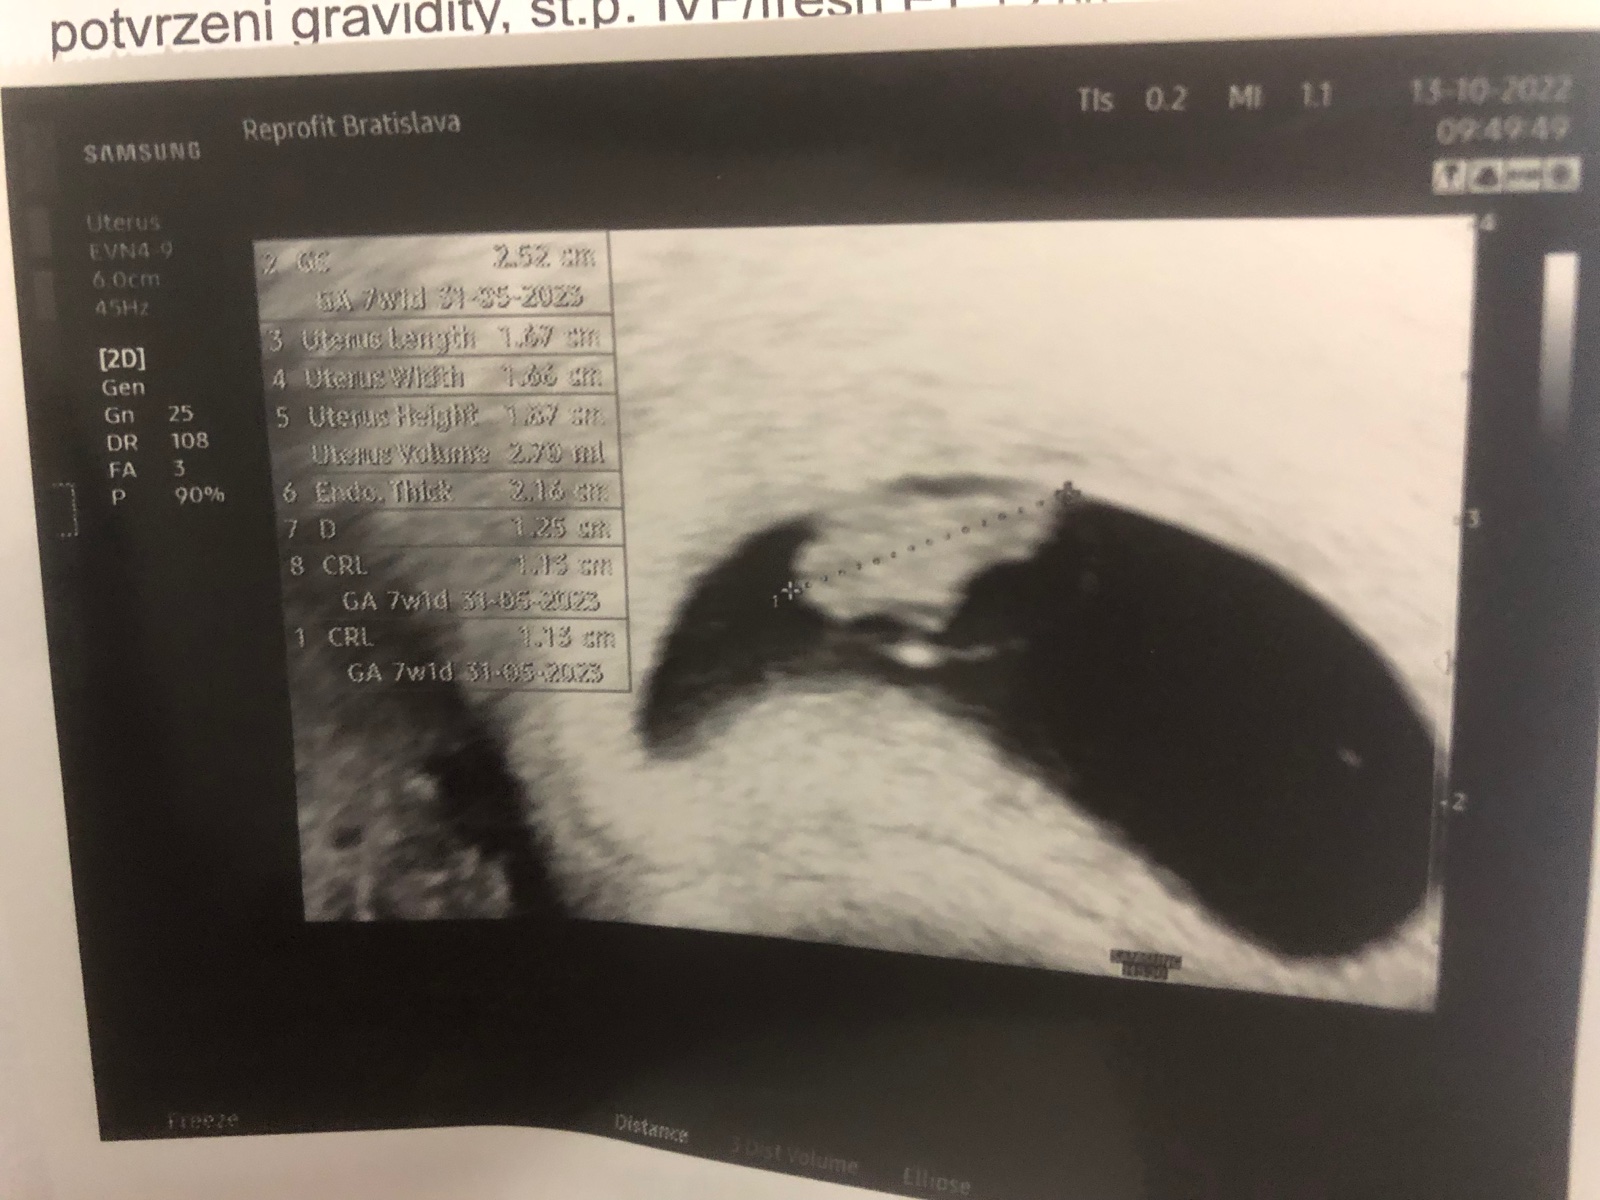

@dorothy13 ahoj,tak sono dnes dopadlo v poriadku presne 7tyzdnov a 1den tehotenstva ako to aj ma byt 🙂 ty si ako na tom?nejake pozitivne tehu testy? 🙂 inak,vy ste ali cez darovane vajicko ked nemas vajcovody?